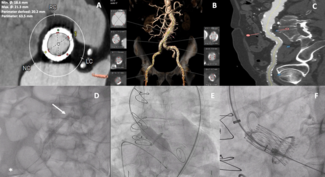

05/04/2026

Ping Hu, MD; Xin-yu Wang, MD; Ming Qi, MD; Jie Wang, MD; Xiao-Jing Ma, PhD

A 55-year-old man presented with medically controlled essential hypertension and a history of abdominal aortic aneurysm stenting 2 years prior who presented with a 3-month history of left lower extremity fatigue on exertion.

Video Supplement to "Late Endovascular Aneurysm Repair Limb Occlusion Presenting as Claudication: Lifelong Surveillance Essential" (Clinical Image).